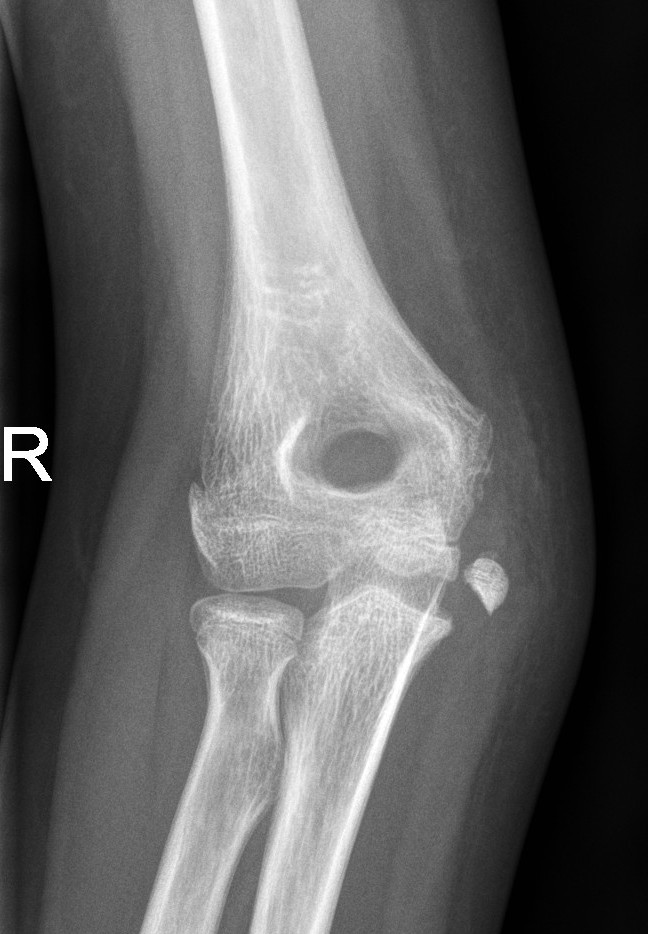

Medial Epicondyle Fractures

- Medial epicondyle fractures are often missed because they are mistaken as an ossification centre. Assess ulnar nerve function in any medial epicondyle fracture.

Undisplaced medial epicondyle fractures

- Above elbow plaster backslab at 90 degrees flexion with follow up in Orthopaedic Fracture clinic in 7-10 days.

Displaced medial epicondyle fractures

- Discuss with the Orthopaedic team for further management.

Displaced medial epicondyle